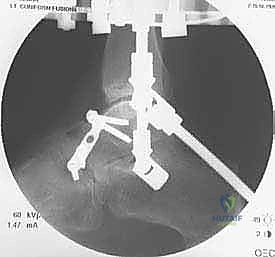

الخطوة الثانية: تركيب الإطار الخارجي (Ilizarov Frame)

هذه هي المرحلة الهندسية الدقيقة. يتم تركيب حلقتين معدنيتين حول عظمة الساق (Tibia) وحلقة ثالثة حول القدم (تثبت في عظمة العقب Talus وعظام مشط القدم).

الخطوة الثالثة: إدخال الأسلاك والمسامير (Wire and Pin Placement)

يتم تمرير أسلاك معدنية رفيعة جداً (Kirschner wires) ومسامير نصفية (Half-pins) عبر العظام لتثبيت الحلقات. يعتمد الأستاذ الدكتور محمد هطيف على معرفته التشريحية العميقة واستخدام جهاز الأشعة المرئي (C-arm) لضمان مرور هذه الأسلاك في "الممرات الآمنة" (Safe corridors) بعيداً عن الشرايين والأعصاب الحيوية.

الخطوة الرابعة: تركيب المفاصل الصناعية (Hinges)

هنا يكمن السر الأكبر للنجاح. يتم توصيل حلقة الساق بحلقة القدم باستخدام مفاصل معدنية قابلة للحركة (Hinges). يجب أن يتم وضع محور هذه المفاصل المعدنية ليتطابق تماماً مع المحور التشريحي الطبيعي لدوران مفصل الكاحل (Center of Rotation of the Talus). هذه الدقة تضمن إمكانية تحريك الكاحل أثناء فترة العلاج دون إحداث ضغط غير متساوٍ على الغضروف.

الخطوة الخامسة: تطبيق التشتيت (Distraction)

أثناء العملية، يقوم الدكتور هطيف بإبعاد حلقة الساق عن حلقة القدم تدريجياً وببطء باستخدام قضبان ملولبة، حتى يصل إلى مسافة تشتيت تبلغ حوالي 5 إلى 6 ملليمترات. يتم التأكد من هذه المسافة عبر الأشعة السينية داخل غرفة العمليات.